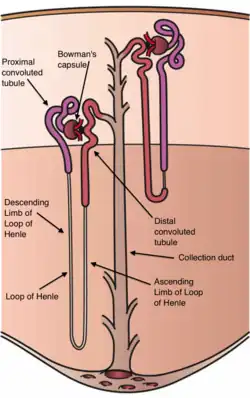

Nephrons, the urine-producing functional structures of the kidney, span the cortex and medulla. The initial filtering portion of a nephron is the renal corpuscle, which is located in the cortex. This is followed by a renal tubule that passes from the cortex deep into the medullary pyramids. Part of the renal cortex, a medullary ray is a collection of renal tubules that drain into a single collecting duct.

The kidneys excrete a variety of waste products produced by metabolism into the urine. The microscopic structural and functional unit of the kidney is the nephron. It processes the blood supplied to it via filtration, reabsorption, secretion and excretion; the consequence of those processes is the production of urine. These include the nitrogenous wastes urea, from protein catabolism, and uric acid, from nucleic acid metabolism. The ability of mammals and some birds to concentrate wastes into a volume of urine much smaller than the volume of blood from which the wastes were extracted is dependent on an elaborate countercurrent multiplication mechanism. This requires several independent nephron characteristics to operate: a tight hairpin configuration of the tubules, water and ion permeability in the descending limb of the loop, water impermeability in the ascending loop, and active ion transport out of most of the ascending limb. In addition, passive countercurrent exchange by the vessels carrying the blood supply to the nephron is essential for enabling this function.

Reabsorption is the transport of molecules from this ultrafiltrate and into the peritubular capillary network that surrounds the nephron tubules.[33] It is accomplished via selective receptors on the luminal cell membrane. Water is 55% reabsorbed in the proximal tubule. Glucose at normal plasma levels is completely reabsorbed in the proximal tubule. The mechanism for this is the Na+/glucose cotransporter. A plasma level of 350 mg/dL will fully saturate the transporters and glucose will be lost in the urine. A plasma glucose level of approximately 160 is sufficient to allow glucosuria, which is an important clinical clue to diabetes mellitus.